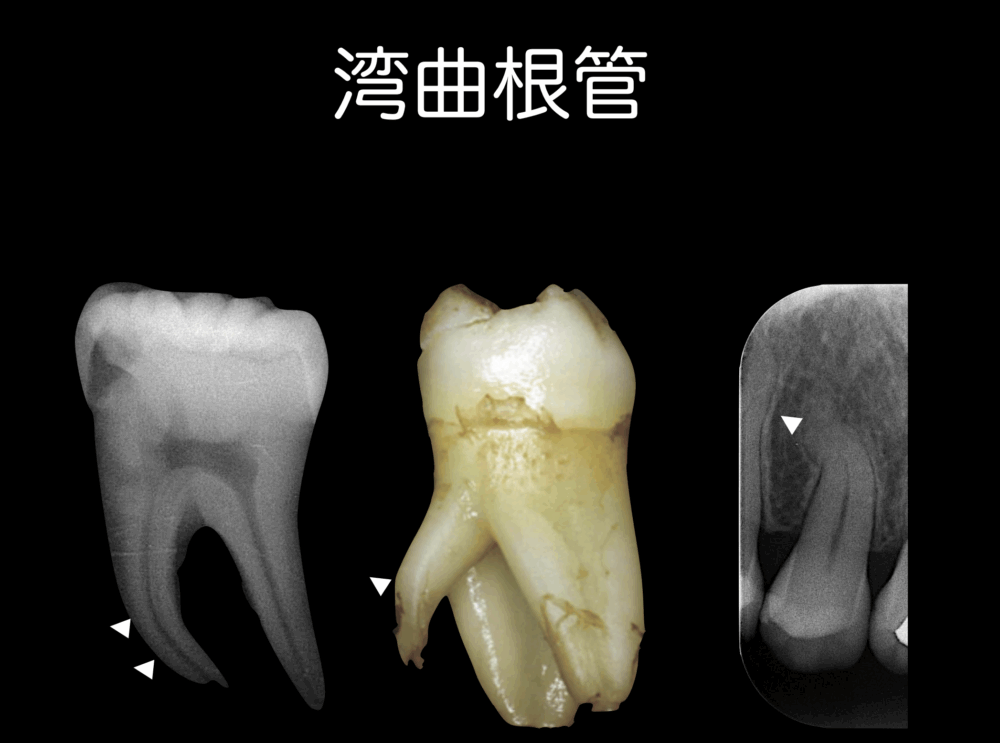

NiTiファイルはステンレススチールファイルに比べると、湾曲根管を形成しやすくなりましたが、NiTiファイルでも太くなると剛性*4が高くなり、下の図のような湾曲根管の根尖まで形成するとなると、ファイルが破折する可能性が高くなります。

では、どのようにしてNiTiファイルの破折する確率を減らし、湾曲根管でも形成しやすくしていったか。NiTiファイルの特徴である弾性と形状記憶効果に工夫をこらして、現在では、湾曲根管でも限界はありますが、以前と比べると破折しにくいように開発されています。